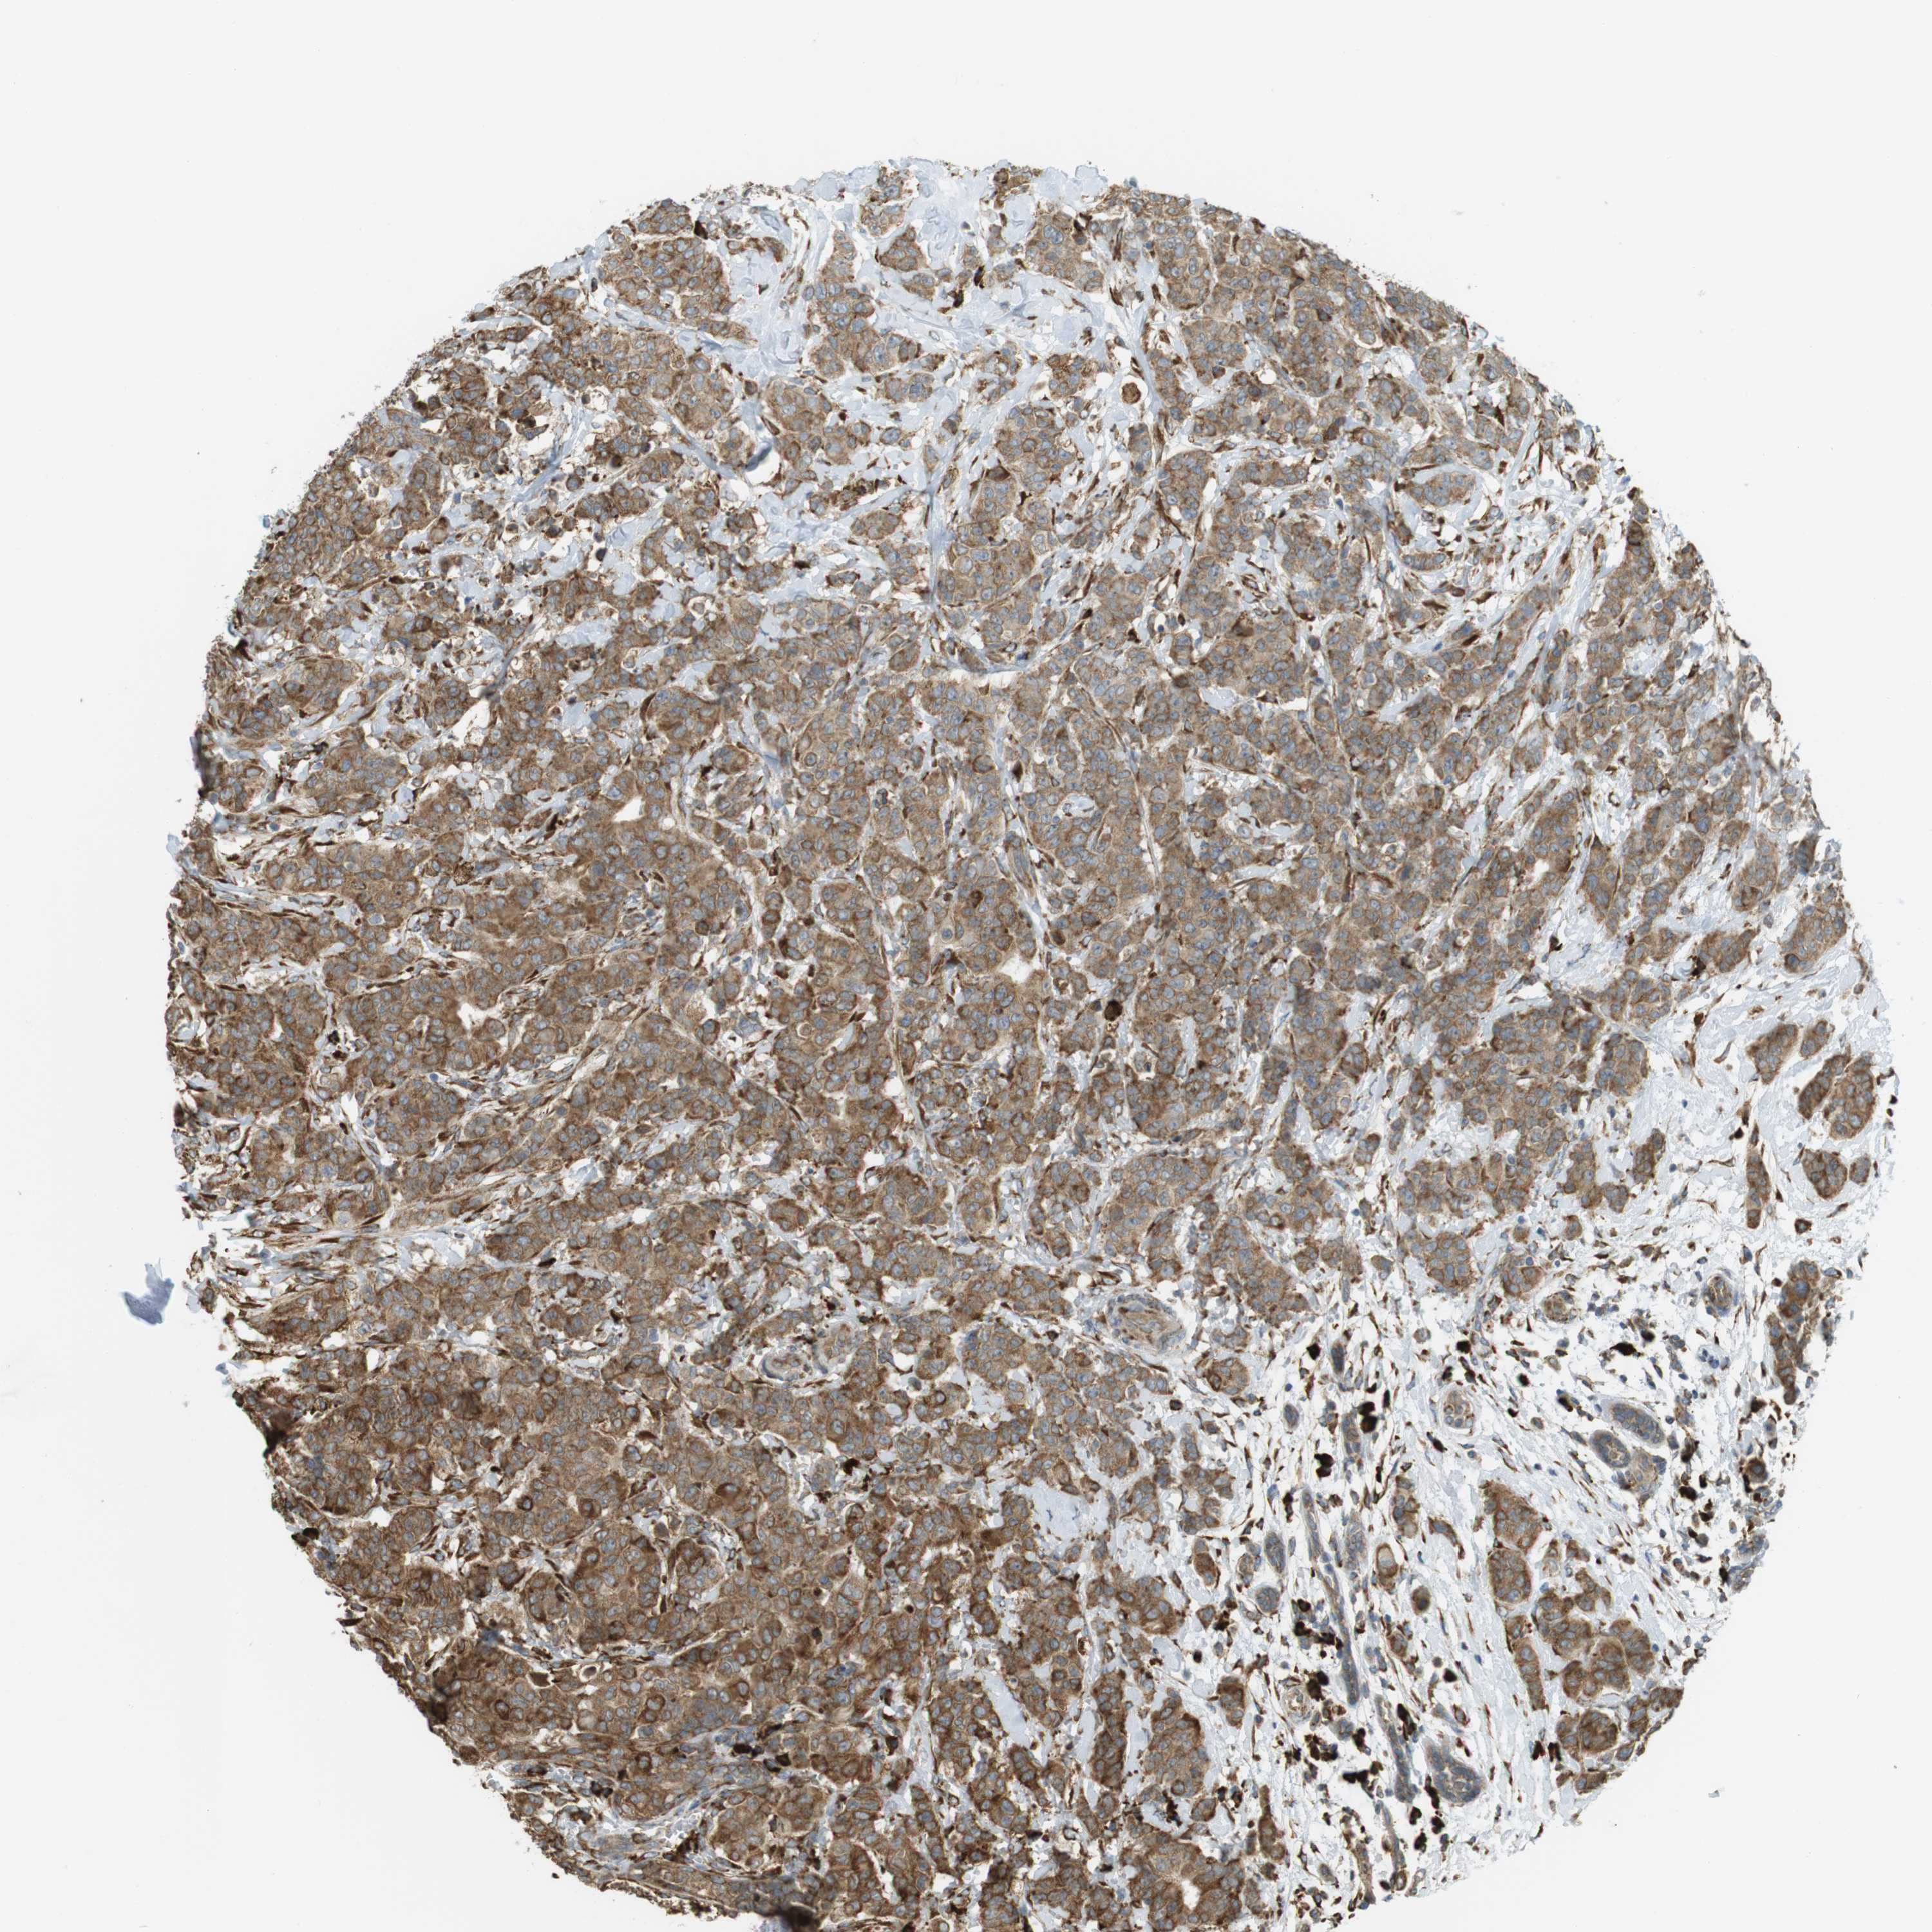

CANCER BREAST CANCER Show tissue menu

BRCA TCGA BRCA VALIDATION PROTEIN EXPRESSION